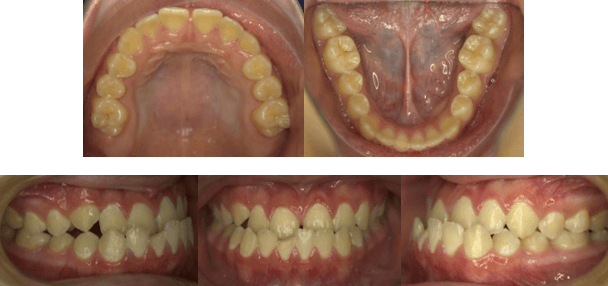

Fotografías Intraorales Iniciales

Diagnóstico Dentario

Maloclusión de Angle: Clase III molar, Clase III Canino, Mordida cruzada anterior

Maloclusión Dewey Anderson: Clase III, Tipo 3

Clasificación de Proffit: 1,2,7

Posiciones dentarias: Retroinclinación del incisivo superior y Proinclinación y protrusión del incisivo inferior